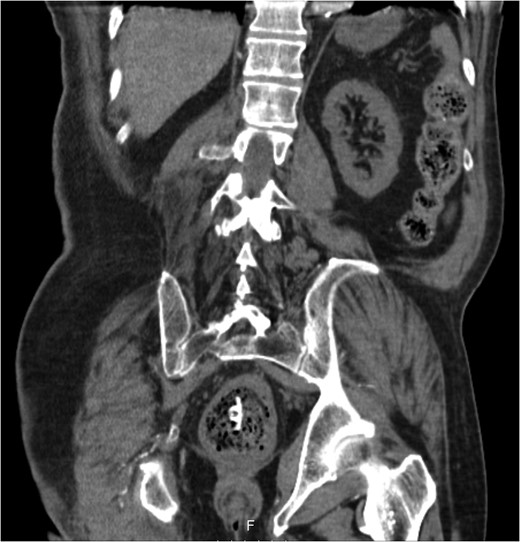

A 68-year-old male nursing home resident presented following dislodgement of a percutaneous endoscopic colostomy (PEC) tube originally sited to prevent recurrent sigmoid volvulus. Computed tomography demonstrated tube migration into the lumen of the recto-sigmoid junction, where it remained for 12 days before passing spontaneously. During this period, the patient remained asymptomatic; the residual colocutaneous fistula functioned as a decompressive valve. Originally, the patient was due to be discharged with early flexible sigmoidoscopy follow-up. However, complex social issues delayed discharge. During his admission, a second PEC tube was successfully inserted next to the previous colostomy site without complication. This is an unusual case and no similar episodes of asymptomatic PEC migration have been reported. We demonstrate that such cases may be offered an appropriate trial of conservative management. Here, we describe our experience and critically appraise the literature.

The PEC tube was inserted 8 months earlier following recurrent sigmoid volvulus requiring repeated flatus tube decompressions. It was intended to provide definitive, long-term management; comorbidities including multiple strokes and poorly controlled diabetes meant more invasive options were unsuitable.

As with other examples [6], this patient's bowel was fixed originally with one PEC. However, effective, long-term prevention typically involves the insertion of two PEC tubes, ideally at each end of the sigmoid colon to reduce mesenteric mobility. This is usually well tolerated with good outcomes [7, 8, 10]. Indeed, in a case where one of two PEC tubes was removed, the patient experienced volvulus recurrence and a second tube had to be re-sited [10].

In our case, only one PEC tube was re-inserted. This was due to technical difficulties at sigmoidoscopy; however, we were reassured by the fact that our patient had not had volvulus recurrence with a single PEC previously. It was thought that the residual colocutaneous fistula tract, obliterated by granulation tissue, may affix the bowel to the anterior abdominal wall at a second location.